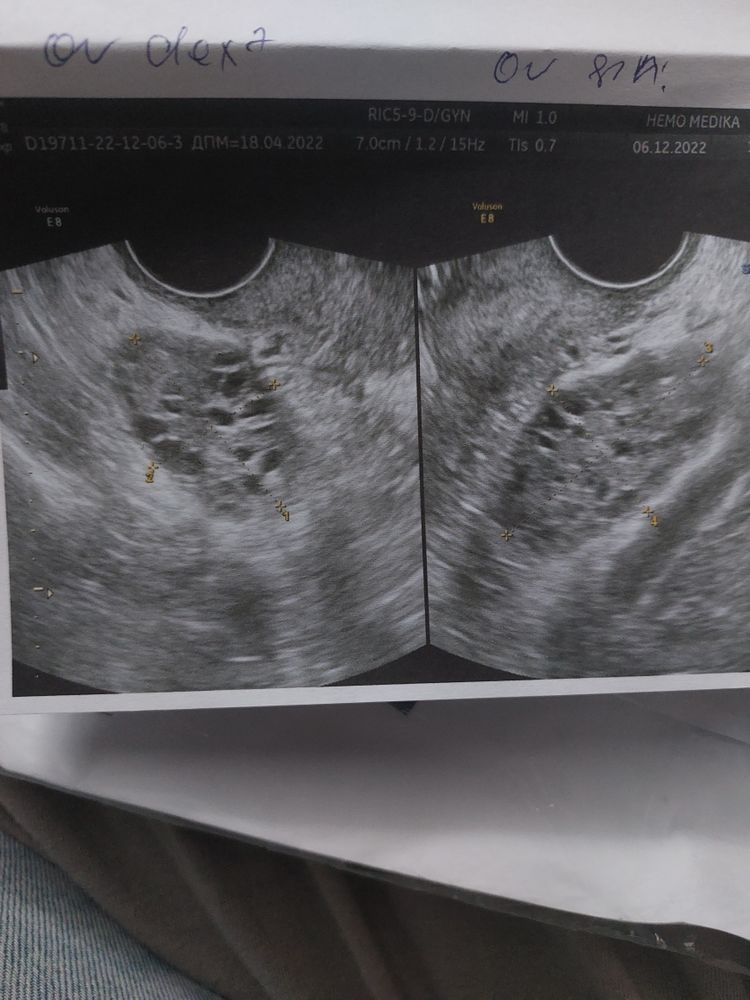

Стимуляция яичников и рост эндометрия: ожидания и надежды

Ну что-ж. Первая стимуляция, и яичники молчат, фоликулы по 4мм. Зато эндометрий подрос 6мм(было4). Ждём 22.12 типа должен начаться цикл, и с 26.12 снова Клостилбегит по 50мг 5 дней. Посмотрим что с этого получиться🙏❤️+ витамины пью: Йодофол и во вторую фазу Енат400